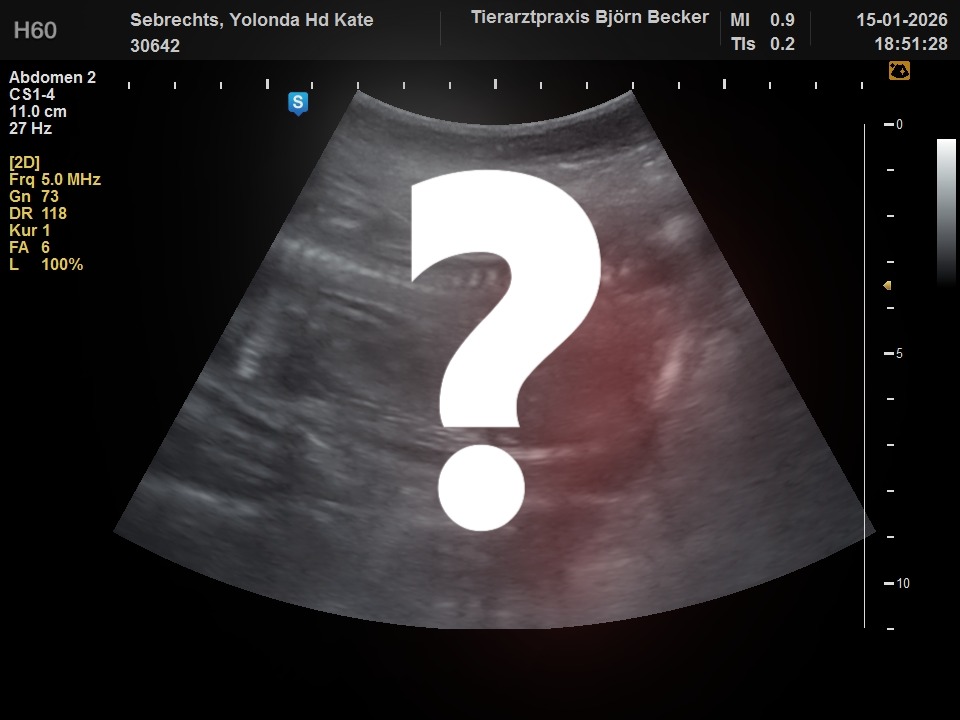

Donderdag 15-01-2026 zijn we met spoed naar de dierenarts geweest. Kate Had wat vruchtwater en slijm verloren. Gelukkig was er niks ergs aan de hand en kwam dit omdat ze veel vruchtwater bij zich heeft. Daarna is er een echo gemaakt. Jullie kunnen nu alvast kennis maken met de puppies terwijl ze nog in de dikke bolle buik van Kate zitten. 6 puppies wilde zich laten zien op de echo en nummer 7 was te verlegen. Over enkele dagen kunnen we ze in het echt zien. Ben je geïnteresseerd en lijkt het je leuk om de puppies te ontmoeten, maak dan een afspraak. De eerste drie weken gaan Kate en wij eerst zelf volop genieten van de puppies. Daarna zijn jullie van harte welkom.

De verlegen pup